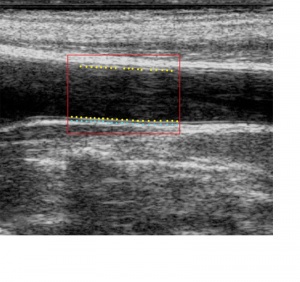

Eine weitere anerkannte Methode zur Charakterisierung der arteriellen Steifigkeit bietet die Bestimmung der Intima Media Dicke (Intima Media Thickness, IMT), bei der die Wandstärke der A. Carotis mittels Ultraschall bestimmt wird. Die weltweit etablierte Methode stellt einen zuverlässigen Indikator der Artherosklerose dar. Die IMT Messung lässt sich zudem mit einer nicht-invasiven Karotis-Druckmessung kombinieren, wodurch die elastischen Eigenschaften der großen arteriellen Gefäße abgeleitet werden können (Elastizitätsmodul nach Young).

Carotid Studio beinhaltet ein Programm zur Echtzeitanalyse von Ultraschall-Bildsequenzen der A. Carotis, wodurch wichtige Parameter der arteriellen Steifigkeit und damit das kardio-vaskuläre Risiko des Patienten abgeleitet werden können. Steht zusätzlich der lokale Pulsdruck zur Verfügung, ermöglicht Carotid Studio gleichzeitig die Bestimmung funktioneller und struktureller Parameter.

- Intima Media Dicke (IMT)

Genauigkeit wie bei Echotracking

Die gesamte Analyse basiert auf einem innovativen mathematischen Algorithmus, der die Grenzen konventionellen bildgebenden Ultraschalls überwindet. Mit dieser neuen Technologie wird eine Genauigkeit erreicht, die bisher nur mit wesentlich aufwändigeren Echotracking Systemen erzielt werden konnte.